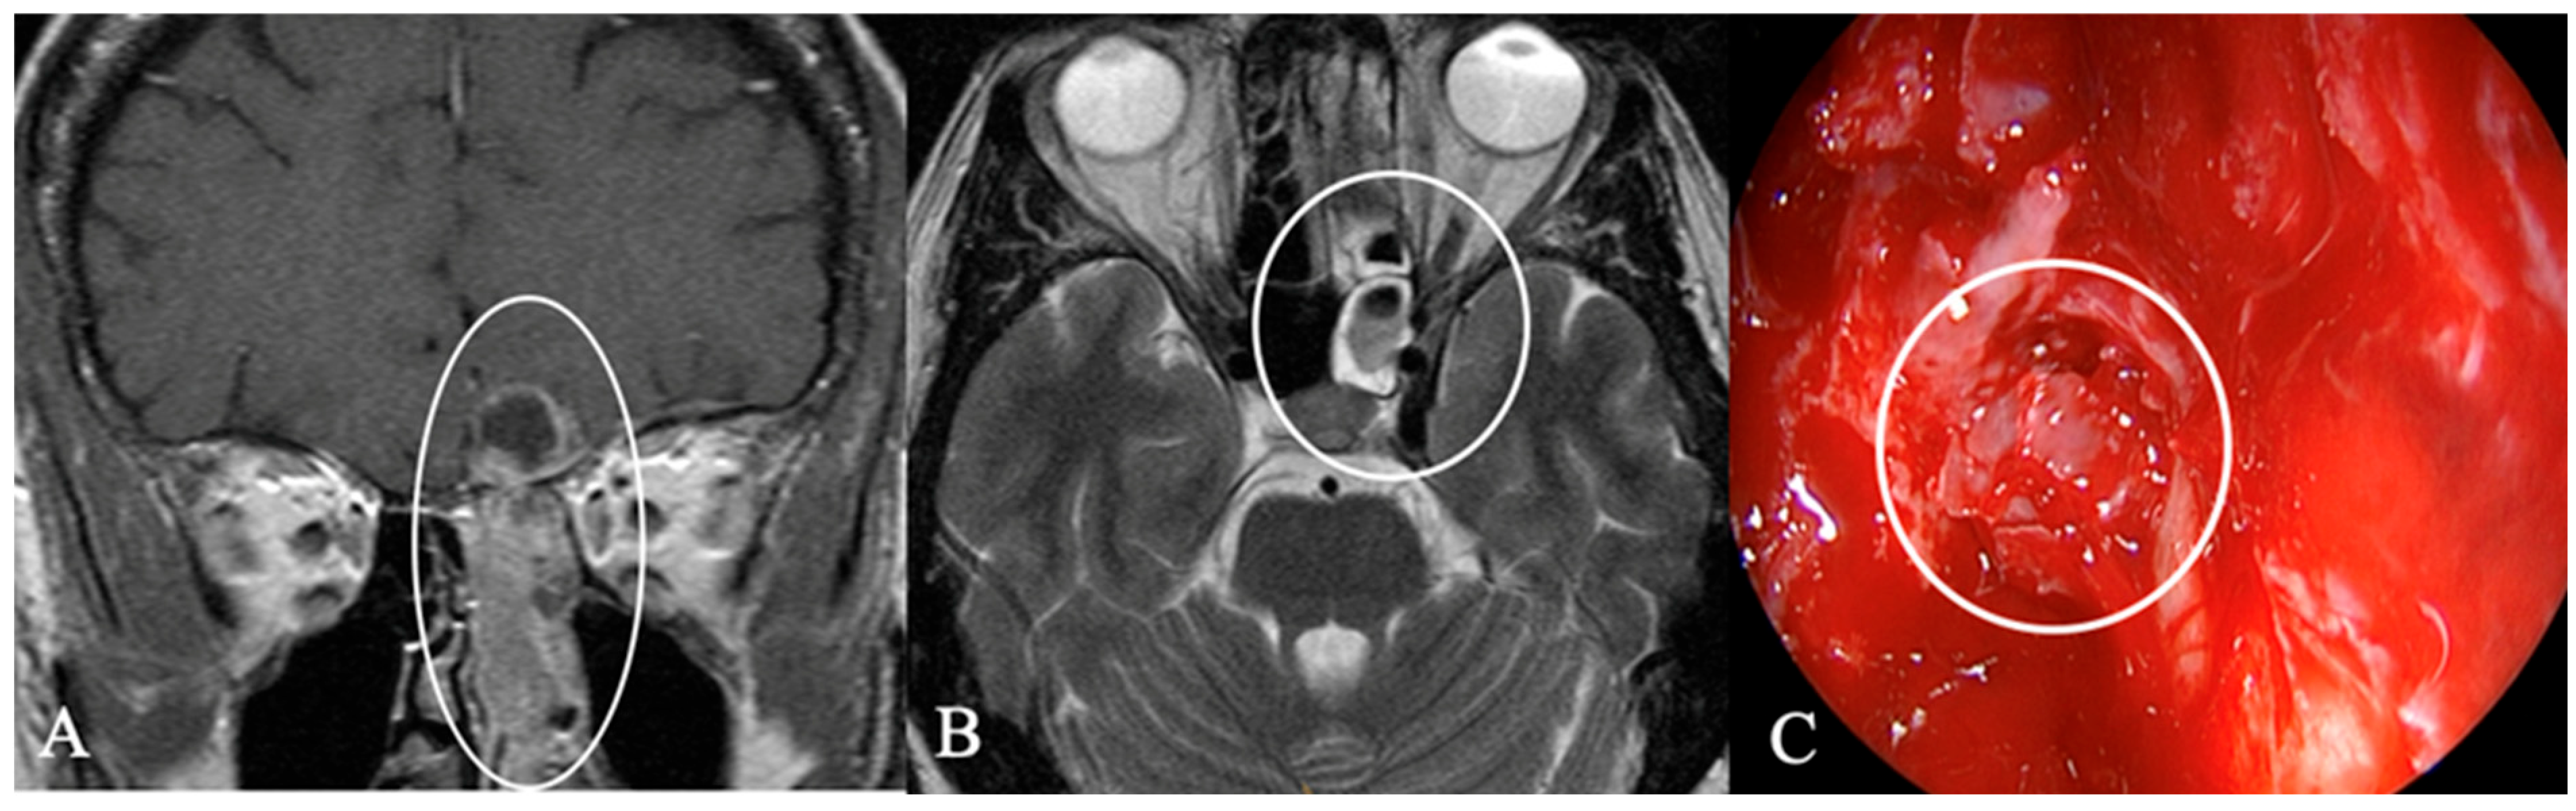

3.3. Imaging Characteristics

| MRI | CT | ||||

|---|---|---|---|---|---|

| Tumor Entity % (n) | Contrast enhancement % (n) | Infundibulum % (n) | Chiasma % (n) | Bone destruction % (n) | Sphenoid sinus infiltration % (n) |

| Dysontogenetic tumors 64% (30) | 43% (13) inhomogeneous 47% (14) marginal | 20% (6) infiltrated | 37% (11) contact 13% (4) compression | 10% (3) osteolytic 7% (2) infiltrated | 17% (5) |

| Pituicytoma 2% (1) | 100% (1) homogeneous | 100% (1) infiltrated | 100% (1) compression | ||

| Metastasis 9% (4) | 75% (3) inhomogeneous 25% (1) homogeneous | 75% (3) infiltrated | 75% (3) compression | 75% (3) osteolytic | 75% (3) |

| Vascular 2% (1) | 100% (1) inhomogeneous | 100% (1) infiltrated | 100% (1) contact | ||

| GII 9% (4) | 25% (1) inhomogeneous 50% (2) homogeneous 25% (1) marginal | 25% (1) infiltrated | 75% (3) contact 25% (1) compression | 25% (1) osteolytic | 25% (1) |

| Carcinoma 6% (3) | 33% (1) inhomogeneous 67% (2) homogeneous | 100% (1) infiltrated | 66% (2) | ||

| Germinoma 2% (1) | 100% (1) inhomogeneous | 100% (1) infiltrated | 100% (1) compression | ||

| Others: 6% (3) | 100% (3) inhomogeneous | 33% (1) infiltrated | 66% (2) osteolytic | 66% (2) | |

| Total: 100% (47) | |||||